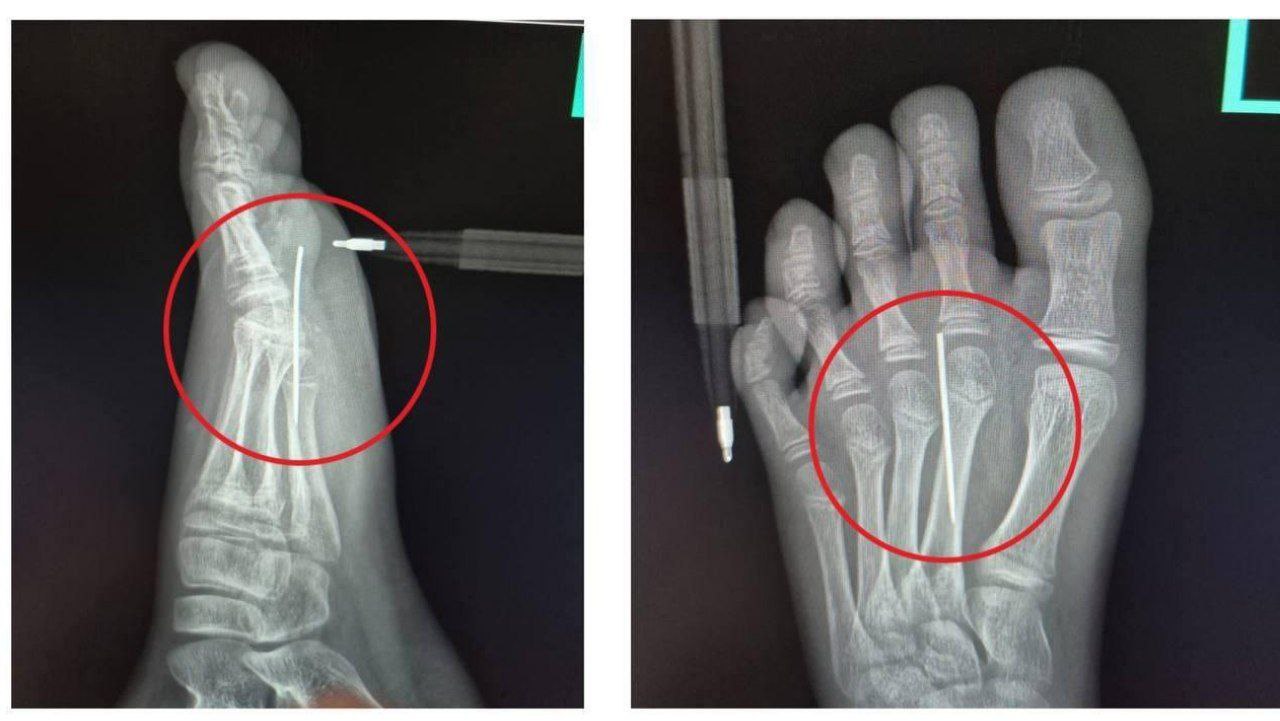

10-летний “участник” перестарался, вырезая фигурки иголкой, и в итоге сам стал жертвой “игры” - игла полностью вонзилась в его стопу!

Спасать юного поклонника сериала пришлось врачам Детского клинического центра имени Рошаля, которые оперативно извлекли инородное тело из его ноги.